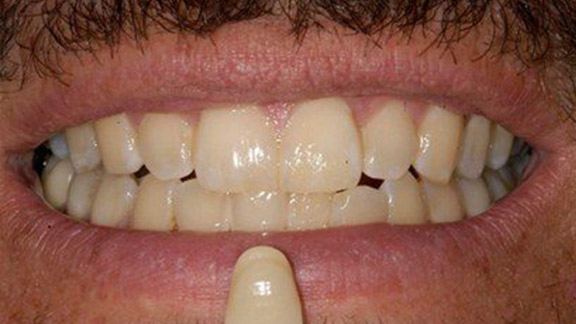

Full Mouth Makeover

Full Mouth Makeover Case 1

Full Mouth Makeover Case 2

Full Mouth Makeover Case 3

Full Mouth Makeover Case 4

Full Mouth Makeover Case 5